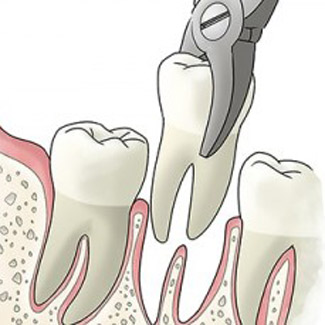

Our first priority is always the repair and retention of your natural teeth. Sometimes this is no longer possible or viable. Extractions include the removal of teeth that are too damaged or decayed to remain without threatening your health. However, Dr. Jane also performs extractions of third molars, better known as wisdom teeth.

Wisdom teeth typically erupt in late adolescence. Unfortunately, allowing wisdom teeth to come in can create serious issues, as the mouth is already full at this point. Wisdom teeth can cause crowding, infections, and other problems if left unchecked.